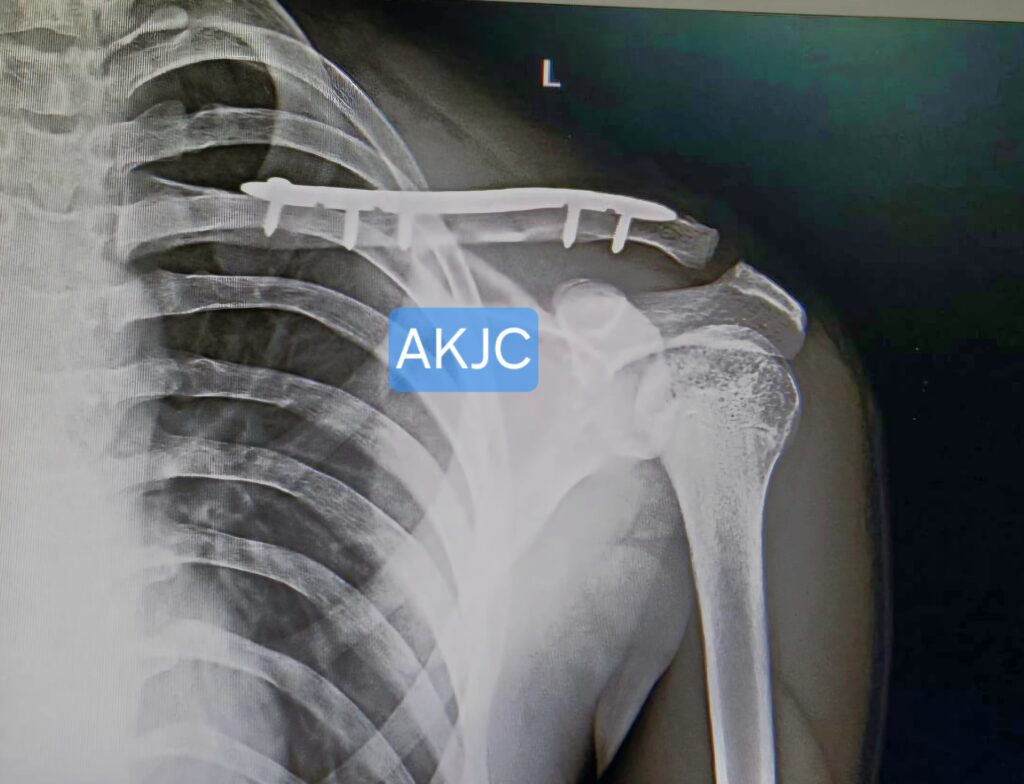

Intra-operative image showing surgical fixation for Clavicle Fracture Treatment in Indore using anatomical plate and screws to restore normal bone alignment.

This method provides strong and stable fixation, allowing early shoulder mobilization. It also helps maintain proper bone length and alignment, which reduces the risk of deformity or non-union. In most cases, the implant does not need to be removed unless it causes irritation.